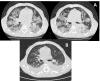

Figure 1

(A) Chest radiographs with diffuse bilateral infiltration; (B) Chest radiographs 15 days post-treatment, with marked improvement of the bilateral infiltrates.

Figure 2

(A) Thorax CT analysis with patchy ground glass haziness in a geographic distribution confirming crazy paving, suggesting of diffuse alveolar haemorrhage; (B) thorax CT analysis 1 month post-treatment, showing minor ground glass haziness.